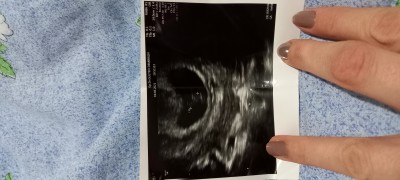

Kızlar çok tuhaf birşeysorucam size instgramda bazı sayfalar varmış üstelik ücretli cinsiyet biliyorlarmış şakamı bu :) ? Öğrenemeyenler için bir arkdasım söyledi bana varmı ona müracat eden açıkcası sistemi çok merak ettim doktorun göremediğini nasıl görüyorlar diye

Gebelik haftası 17

Saglıkla doğsun ibŞallah benım de soru postuma ekledim usg fotosu bakarmısınıx acaba :))

Yanlış görmüyorsam sola doğru yerleşmiş miniş, benimkinin tam tersi yani. Eğer vajinal ultrasonla bakıldıysa kız olabilir :))

normal karın usg si ile bakıldı evet sola daha yakın görünuyor karın usg sinde de aynımı acaba hiç anlamıyorum ki bu işlerden :)) benim doktorum çok garanticiydi benzede dahi söylemez doktor değiştirdim malesef birazda iletişim sorunu yaşadık :/